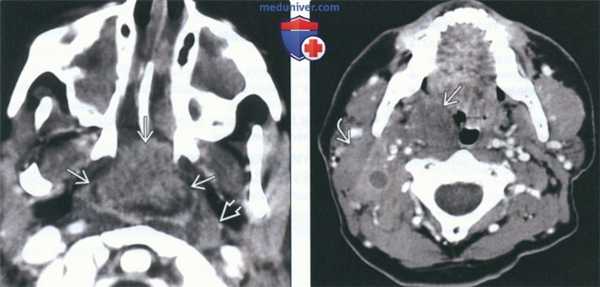

(Слева) На аксиальной КТ с КУ у ребенка со СПИДом определяется массивная аденоидальная НХЛ с неравномерным накоплением контраста. Обратите внимание на крупный заглоточный лимфоузел слева и практически полную окклюзию просвета носоглотки. Обе верхнечелюстные пазухи и полость носа заполнены секретом (доброкачественные изменения).

(Справа) На аксиальной КТ с КУ определяется мультифокальная НХЛ с вовлечением миндалины справа и лимфоузла II уровня с экстранодальным распространением. Шейная лимфаденопатия присутствует более чем в 50% случаев НХЛ слизистой оболочки глотки (СОГ).

(Слева) При КТ с КУ в аксиальной проекции у ребенка со СПИД в области глоточной миндалины определяется крупная неходжкинская лимфома, неоднородно накапливающая контраст. Обратите внимание на увеличенный лимфоузел в заглоточном пространстве слева и на практически полную обструкцию просвета носоглотки. Полость носа и верхнечелюстные пазухи с обеих сторон заполнены доброкачественным секретом.

(Справа) При КТ с КУ в аксиальной проекции визуализируется мультифокальная неходжкинская лимфома с вовлечением правой небной миндалины, а также группа спаянных лимфоузлов II уровня. Шейная аденопатия встречается в 50% случаев неходжкинских лимфом слизистого окологлоточного пространства.